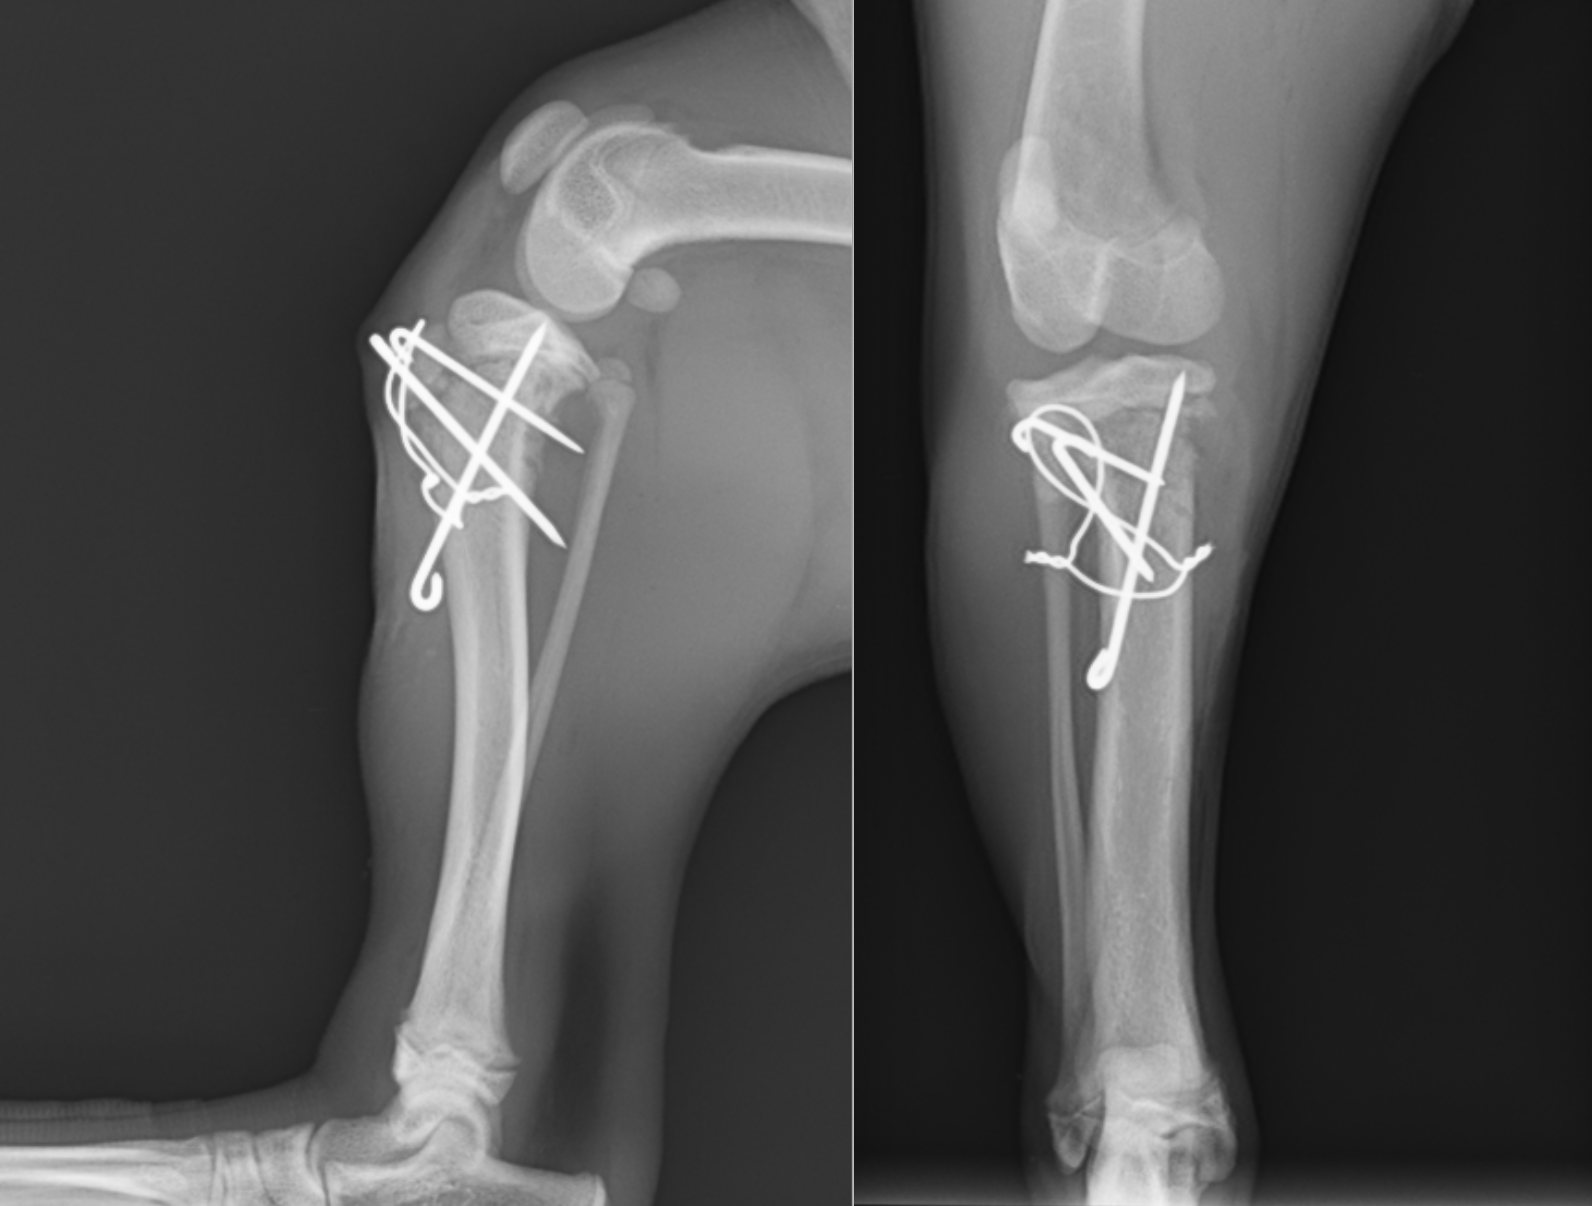

手術ではまず、ずれてくっついてしまった骨を剥がすところから始まります。1週間でもかなり癒着が進んでいたため、それを一度剥がし、正しい位置に戻しました。骨折の固定には一般的にプレートスクリューを用いることが多いですが、成長板骨折の時は別で、成長板をまたいだ固定は禁忌とされているため(成長が阻害され骨が伸びなくなってしまう)、キルシュナーワイヤーとテンションバンドワイヤーという方法により固定を行いました。術中はCアームと呼ばれるレントゲン透視装置を用いて、正しい位置にピンが刺入されているかを確認しながら手術を行いました。

術後のレントゲン画像です。ずれていた骨片は正しい位置に戻っているのがわかると思います。左下から右上に打っているピンは、骨片が右にずれないようにするストッパーのような役割をしています。